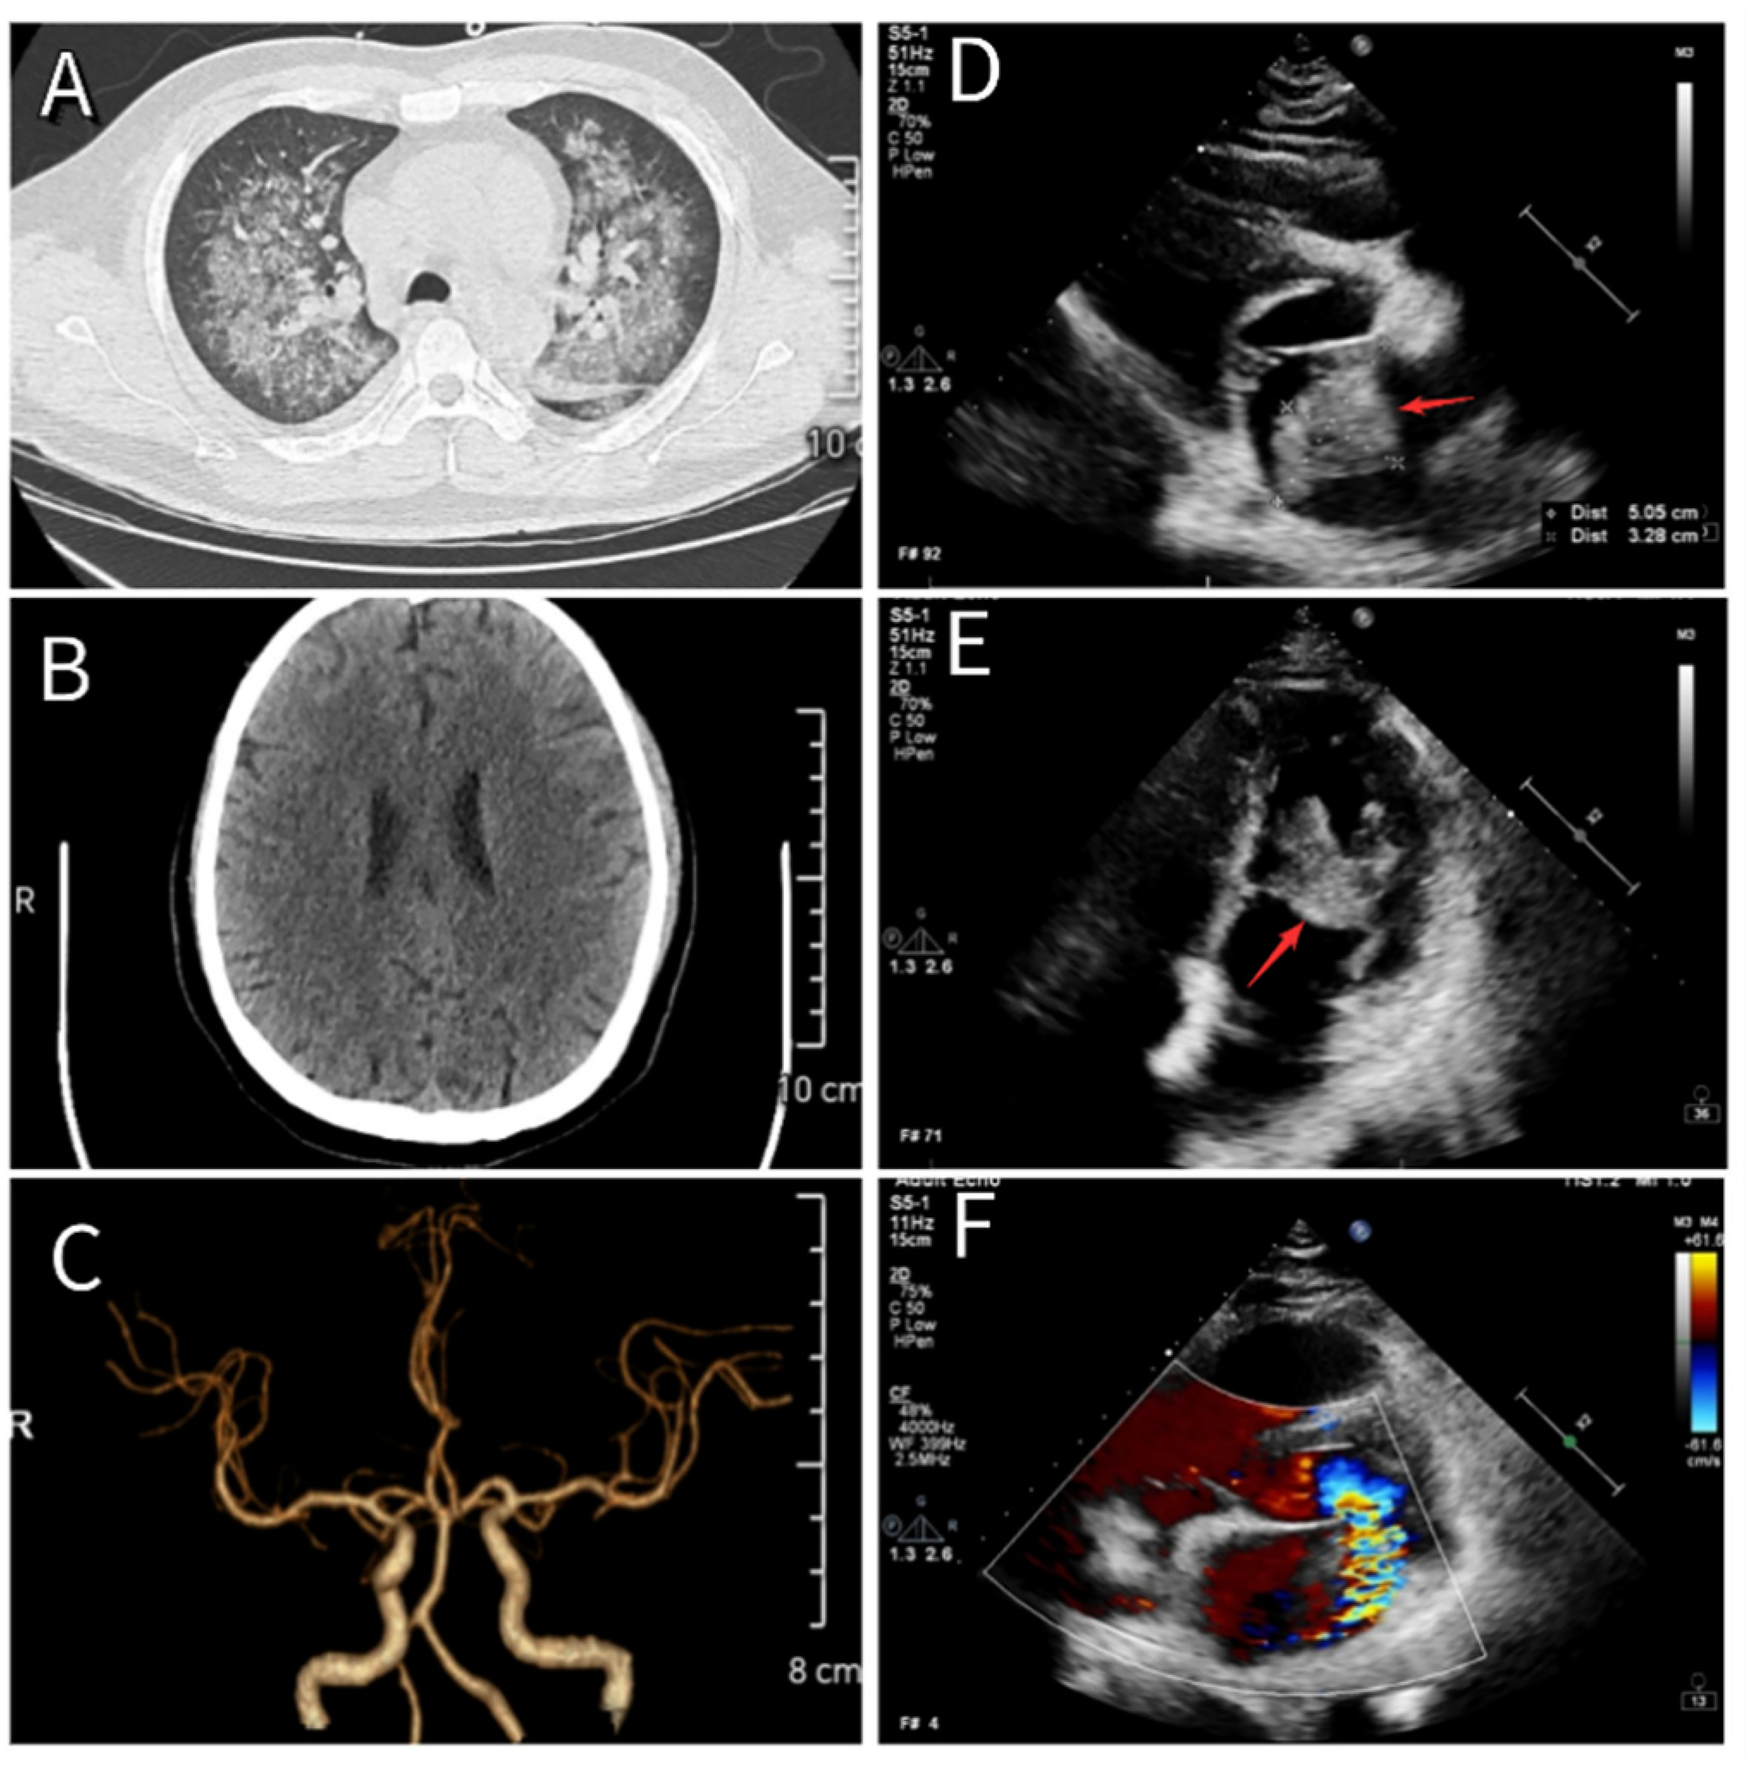

His medical history included more than 2 years of hypertension, managed with sacubitril/valsartan, and no other notable conditions. On physical examination, the pulse was 136 beats per minute, respiratory rate 22 breaths per minute, blood pressure 106/59 mmHg, and body temperature 38.5°C. Auscultation revealed widespread fine crackles in both lungs, a regular heart rhythm, and a newly detected low-pitched diastolic murmur at the apex. No significant edema was present in the lower limbs. A continuous blowing murmur was heard over the arteriovenous fistula in the left forearm. The initial diagnoses were infectious fever, severe pneumonia (Figure 1A), chronic kidney disease stage 5, secondary hypertension, and hemodialysis status.

Figure 1

(A) Chest CT showing changes consistent with severe pneumonia. (B) Cranial CT showing no evidence of cerebral infarction. (C) Cranial CTA revealing normal cerebral vasculature. (D,E) Echocardiographic images showing a newly identified atrial mass located at the root of the anterior mitral leaflet, measuring approximately 51 mm × 33 mm × 32 mm (red arrow). (F) The mass moves between the left atrium and ventricle with each cardiac cycle, resulting in severe mitral regurgitation.

Based on the diagnosis of infectious fever and severe pneumonia, the patient was started on intravenous piperacillin-tazobactam (4.5 g every 12 h) and vancomycin (0.5 g once daily) to provide broad coverage for both Gram-positive and Gram-negative organisms, along with supportive therapy. On the evening of May 24, 2024, he developed acute confusion, delayed responses, and significant chest tightness accompanied by dyspnea. Emergency consultations with neurology and cardiology were initiated. Given the brief onset time, cranial computed tomography angiography (CTA) showed no apparent vascular abnormalities or cerebral embolic lesions (Figures 1B,C). Cardiac auscultation by the cardiologist revealed a characteristic “tumor plop” sound at the apex, leading to immediate bedside transthoracic echocardiography. The scan detected a heterogeneous echogenic mass in the left atrium, approximately 51 mm × 33 mm × 32 mm in size (Figures 1D,E), raising suspicion for either a vegetation associated with IE or an atrial myxoma. Blood cultures collected on May 25 confirmed a bloodstream infection with Rothia dentocariosa. Serial tests showed a rising trend in cardiac troponin, persistent fever, elevated inflammatory markers, and other abnormalities (see Table 2).